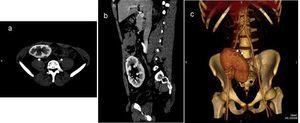

Presentamos un caso mediante imágenes de un carcinoma papilar renal multicéntrico en un riñón trasplantado detectado mediante un estudio de seguimiento ecográfico rutinario, en un paciente de 29 años de edad, dos años después del trasplante (figura 1, figura 2 y figura 3).

Figura 2. Imágenes obtenidas a partir de una tomografía computarizada helicoidal de 64 detectores